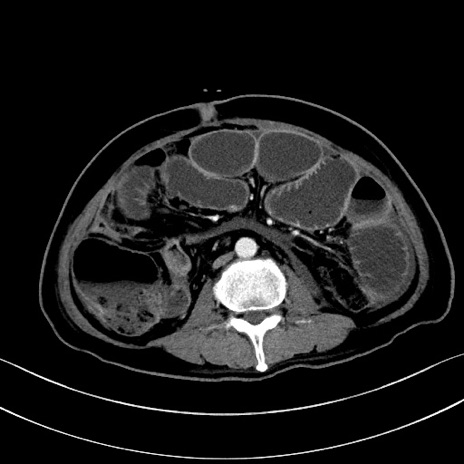

症例28(横断像)

【症例】60歳代男性

【主訴】嘔吐

【現病歴】胃癌にて胃全摘後。食思不振が悪化し、夜中に嘔吐することがある。

【既往歴】胃癌、胃全摘、脾摘、胆摘後

【データ】WBC 5900、CRP 10.56